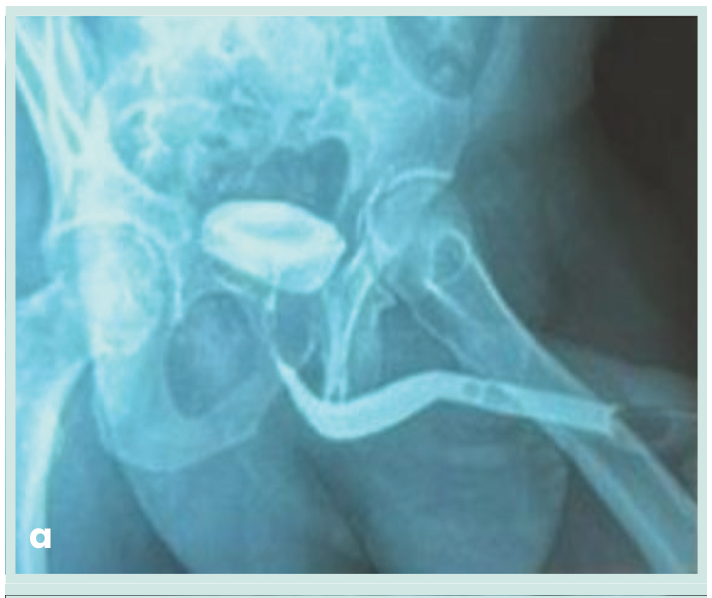

• Estudios complementarios: uretrocistografía retrógrada: contorno regular de la uretra, sin defectos de llenado ni reflujo vesicoureteral (Figura 2a, 2b y 2c). Panel de infecciones de transmisión sexual por PCR: negativo. Procedimiento: se realizó exéresis quirúrgica completa de la lesión bajo anestesia local.